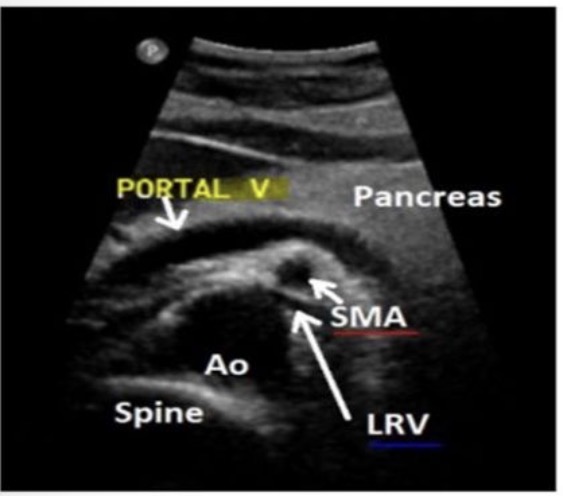

PV location in relation to the pancreas

PV is shown posterior to the head of the pancreas

SMA in relation to the pancreas

SMA is sandwiched between the aorta and splenic vein

left renal vein location in relation to the pancreas

LRV is anterior to the aorta and posterior to the SMA